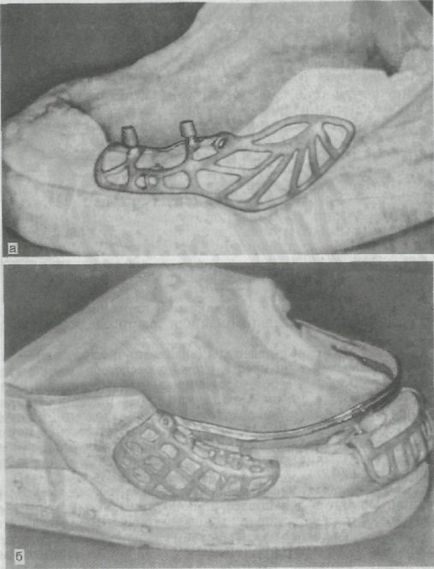

2. Subperiosteal implantátumok (subperiosteal) fém keretek ötvözetből nemesfém ötvözetek vagy rozsdamentes acél. Anyaguk alapján egyedileg anatómiai leadott lövés skeletonized alveoláris rész. A telepítés után az illeszkedés és a fedél kerettel helyet előre az elválasztott mucoperiosteal szárnyak és varrt. Keresztül a csappantyú a szájüregben a fém csapok, amely szolgálhat a támogatása rögzített hidak vagy kiegészítő tartóelemek számára kivehető fogsor. Ezeket fel lehet használni mind a felső és az alsó állkapocs, de a legtöbb esetben alkalmazott subperiosteal implantátumok a mandibula (ábra. 278).

Ábra. 278. subperiosteal implantátumokat.

és - keretében egyoldalú subperiosteal implantátum a modellt; b - a bilaterális subperiosteal implantátum modell szerint.